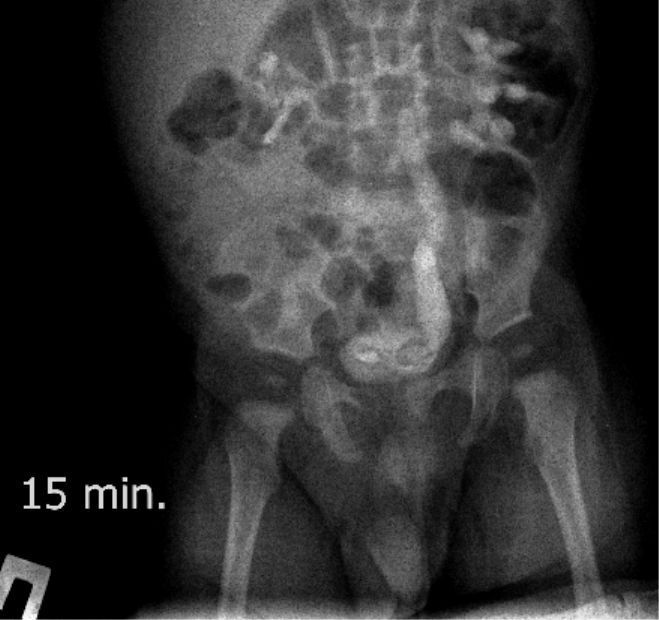

Экскреторные урограммы данного пациента :

На всех снимках определяется левосторонний уретерогидронефроз 3-й степени и левостороннее уретероцеле непостоянного размера. Справа - расширения собирательной системы почки не выявлено. На снимке на 15 минуте после введения контраста определяется уретероцеле справа небольших размеров, на последующих снимках достоверного его контрастирования нет.